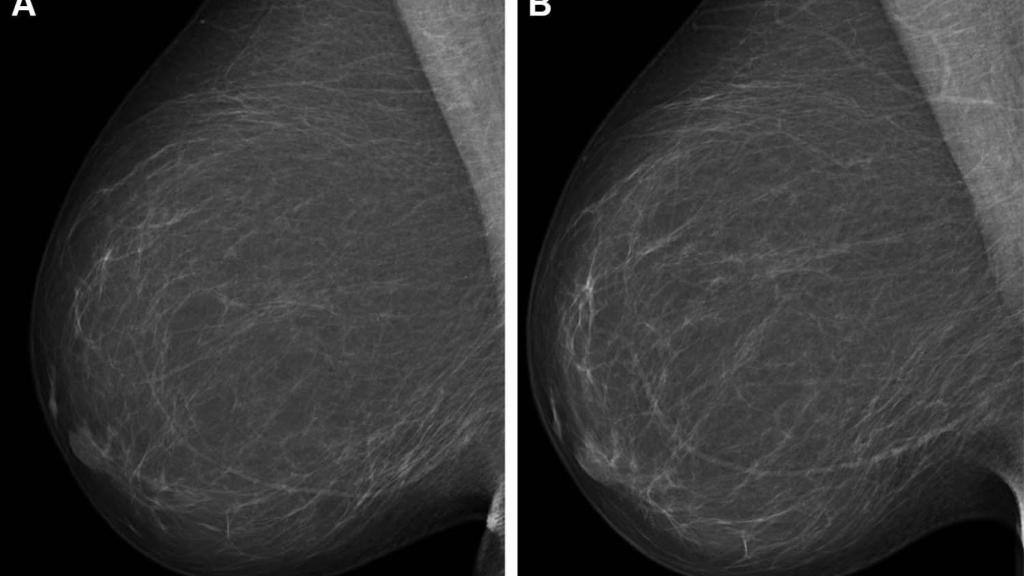

Mamografía en una imagen de archivo.

Mamografía en una imagen de archivo. EP Sevilla